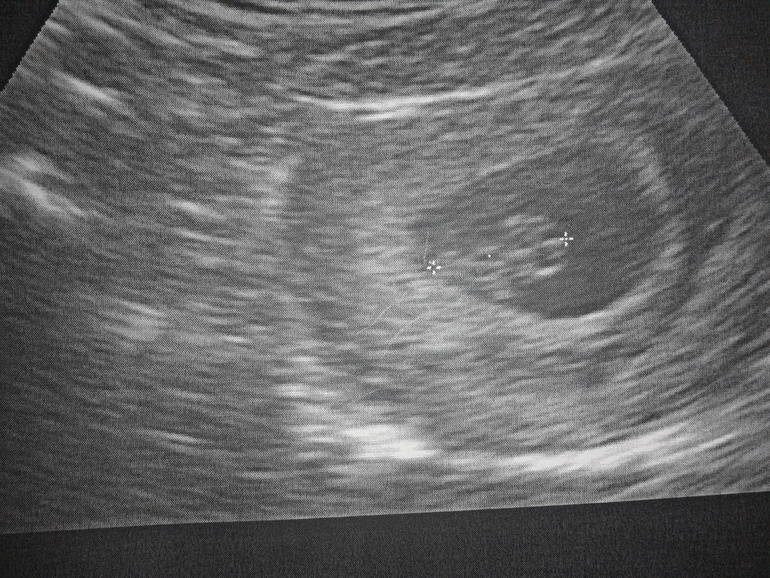

мы познакомились с нашим малышом))))

Спасибо) да,мы впервые увидели нашего малыша))) на учет встала в 6 недель,сейчас 8